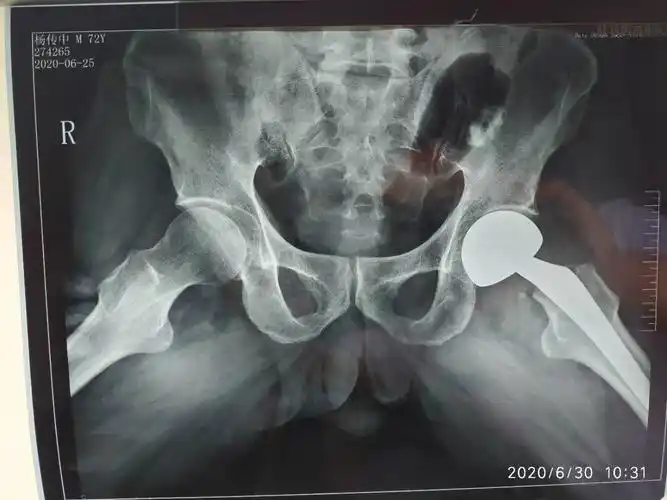

术后髋关节蛙式位,假体位置适中.